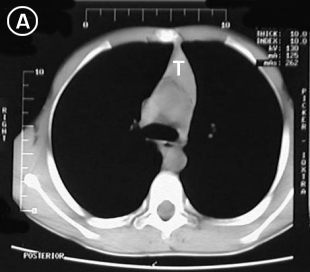

Tomografia A Tomografia B

Estudio tomografico milimetrico, progresivo desde el vértice hasta bases pulmonares, en donde no se apreciaron procesos pleuro-parenquimatosos; Mediastino sin adenopatías; En los cortes pretraqueales (A) y (B) se aprecia imagen de densidad de partes blandas en correlacion con probable timo hiperplasico y/o timoma, extendiendose distalmente anterior a los grandes vasos (C), observese su ausencia en el corte precordial inferior (D), donde apreciamos una silueta cardiaca de morfologia conservada, las bases pulmonares y el hemi-abdomen superior no mostraron alteraciones.

Tomografia C Tomografia D